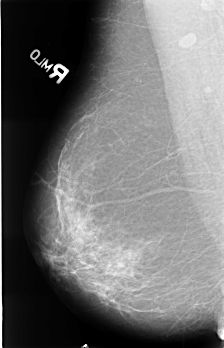

B_3476_1.RIGHT_MLO

RIGHT_MLO LINES 4520 PIXELS_PER_LINE 2904 BITS_PER_PIXEL 12 RESOLUTION 50 NON_OVERLAY